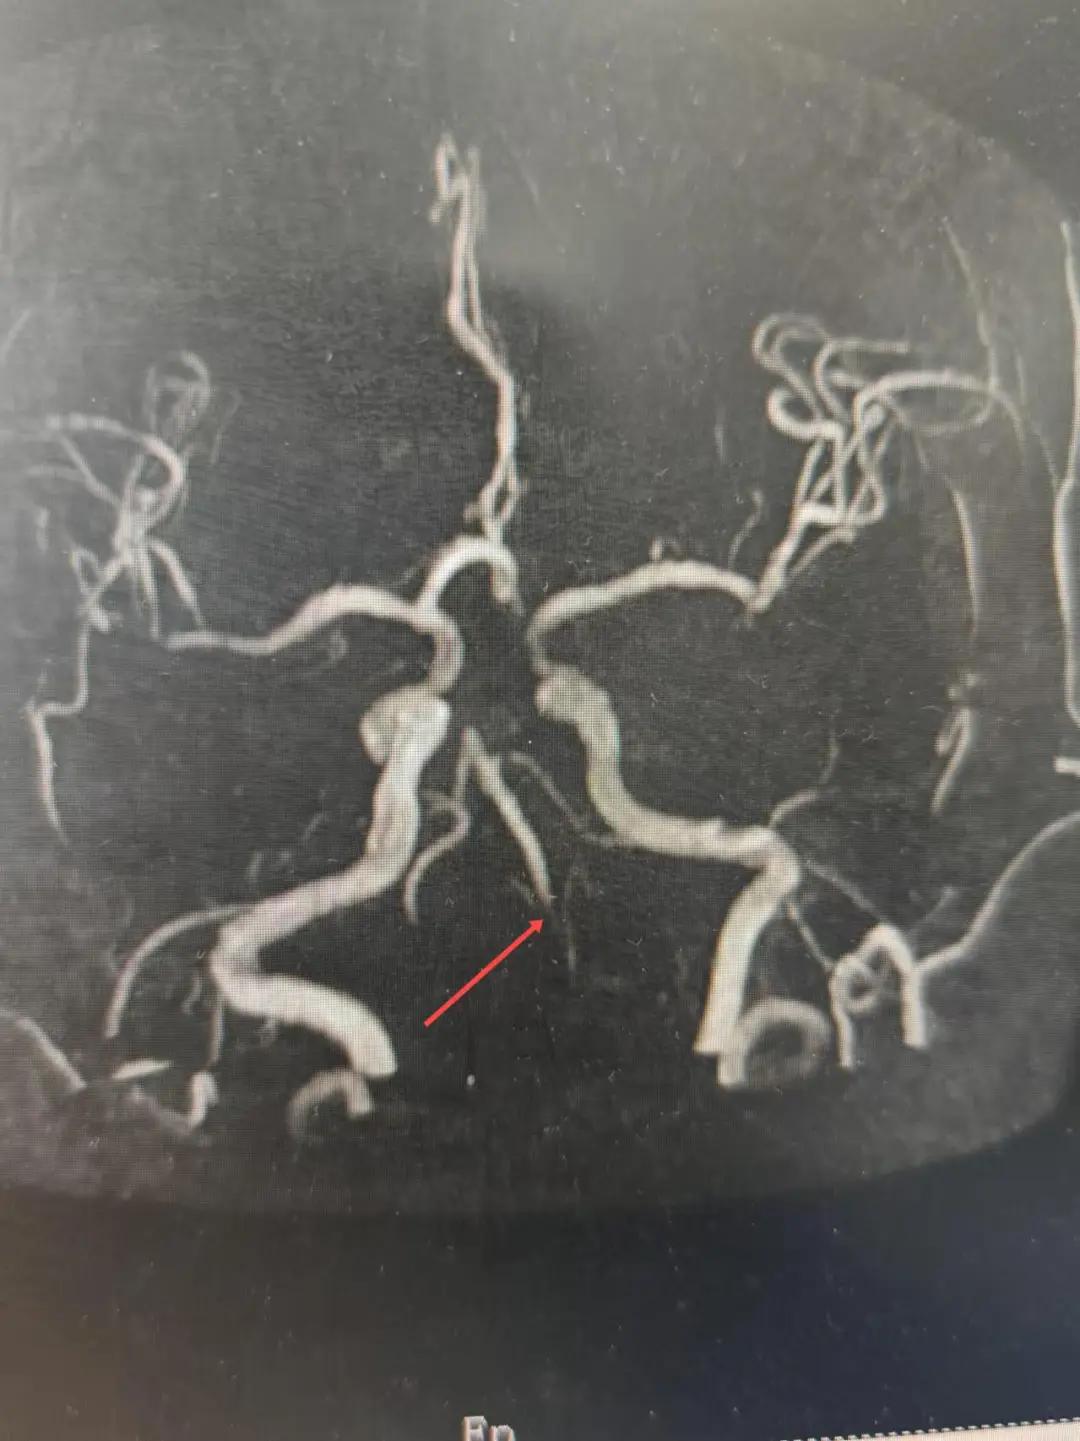

2024年12月19日,漯河市中醫(yī)院腦一科收治了一位79歲的女性患者。患者在入院前2小時(shí)出現(xiàn)言語不利,右側(cè)肢體無力。腦一科醫(yī)師關(guān)卓杰接診后,全面評估患者病情,給予其靜脈溶栓,并急查頭顱MR。影像可見腦干、雙側(cè)枕葉、左側(cè)海馬旁回及丘腦新發(fā)梗塞灶,基底動(dòng)脈閉塞。患者在靜脈溶栓完畢后仍出現(xiàn)陣發(fā)性言語不利、右側(cè)肢體無力、頭暈。立即進(jìn)行科室間會(huì)診,副主任醫(yī)師彭壯考慮患者出現(xiàn)上述癥狀與其基底動(dòng)脈閉塞后顱內(nèi)動(dòng)脈代償不良有較大關(guān)系,且基底動(dòng)脈閉塞有較高的致死率與致殘率,建議行急診取栓,降低患者死亡及殘障風(fēng)險(xiǎn)。家屬了解病情,知情同意后要求行介入治療。

磁共振MRA提示基底動(dòng)脈閉塞